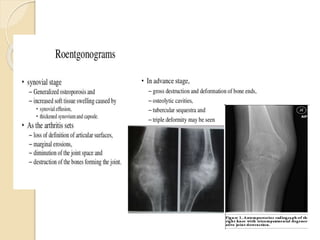

PATHOLOGY & PATHOGENESIS Any osteo-articular TB is the result of hematogenous dissemination from a primarily infected visceral focus.  Reach the joint space via bloodstream through subsynovial vessel or from the lesions in the epiphyseal bone.  Destructions begins peripherally  The initial focus starts in the metaphysis in growing age or the end of the bone in adult.  The articular cartilage loses its nutrition & attachment when subchondral region is involved.

 Synovial membranebecome swollen & congested with synovial effusion.  Granulation tissue from synovium extends to joint.  “Pannus” is formed at the periphery by the granulation tissue.  “Rice bodies” in the joint.  “Kissing lesion” on each side of the joint.